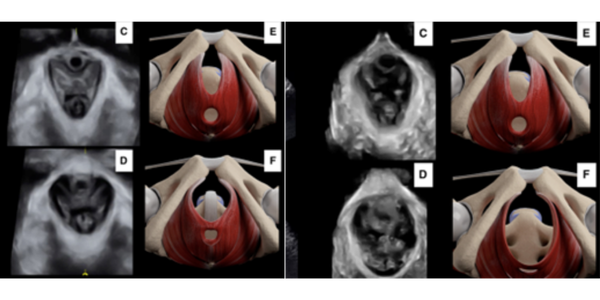

Ahora damos un paso más, además de la ecografía funcional en 2D introducimos la ecografía funcional en 4D. Este tipo de ecografía nos permite ver las estructuras anatómicas con volumen en tiempo real y calcular áreas anatómicas concretas, lo que amplia nuestras posibilidades de valoración y potencia nuestros resultados.

Mediante la ecografía funcional en 4D podemos valorar esta capacidad funcional en cada mujer para detectar aquellas mujeres que necesitan reeducar esta función antes del parto y con ello minimizar los riesgos. La reeducación se basa en el uso de la ecografía como sistema de biofeedback, consiguiendo que cada mujer sea capaz de realizar pujos de forma eficaz y segura.

Sumada a toda la información de la ecografía funcional en 2D, añadimos la información que nos aporta la ecografía funcional en 4D respecto a los músculos del suelo pélvico y los esfínteres Podemos observar la respuesta de los tejidos en tiempo real, conocer las medidas morfométricas de los músculos del suelo pélvico, la posición de los músculos dentro de la pelvis menor, la posición de la vejiga, el recto, el útero, la capacidad vesical, el control motor etc.